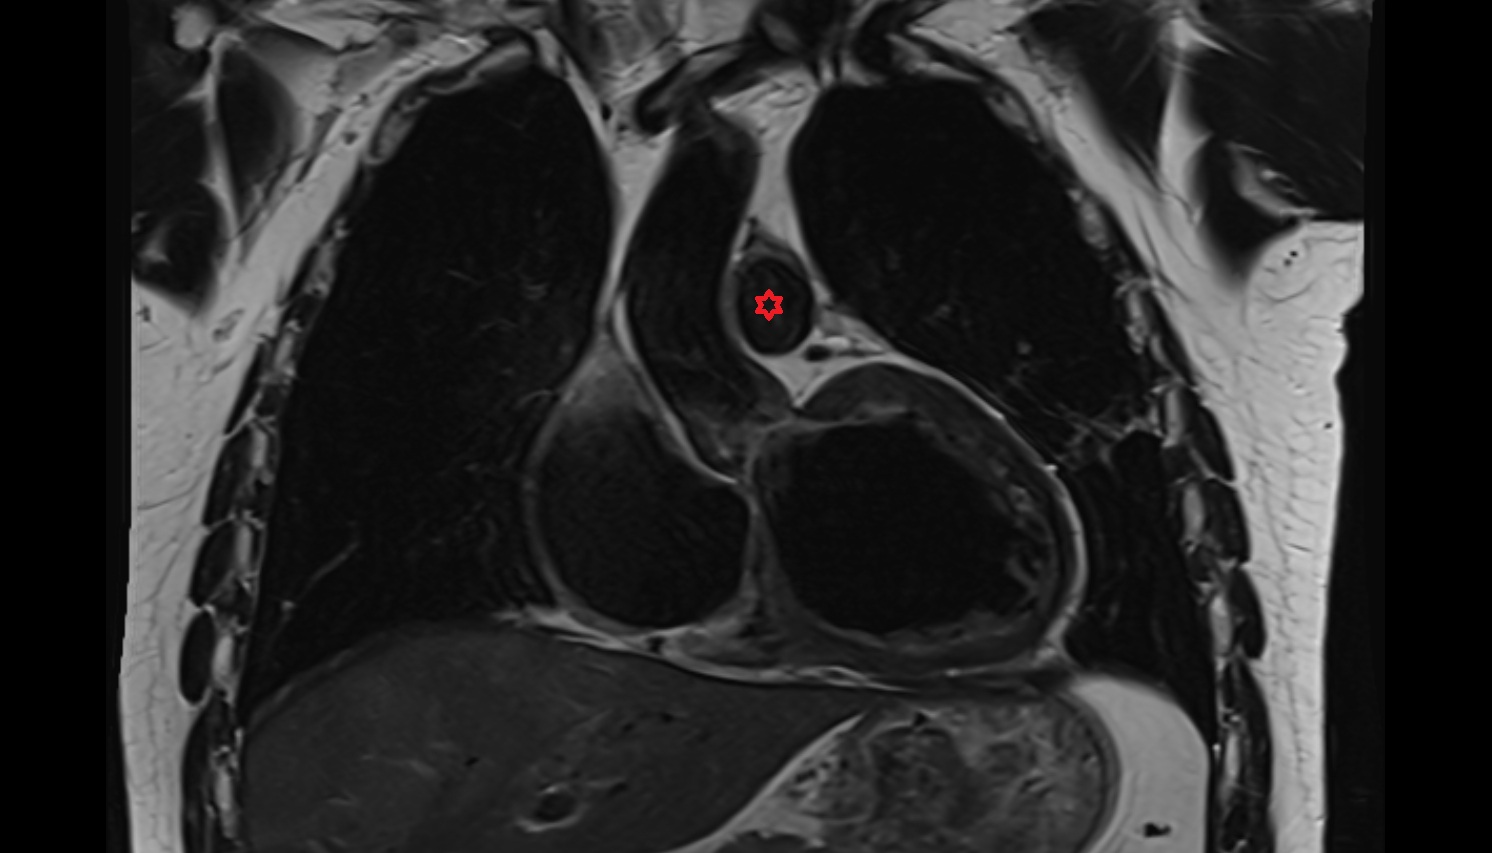

- Pericardium

- Heart

- Left ventricle

- Right atrium

- Left atrium

- Right ventricle

- Pulmonary trunk

- Interventricular Septum